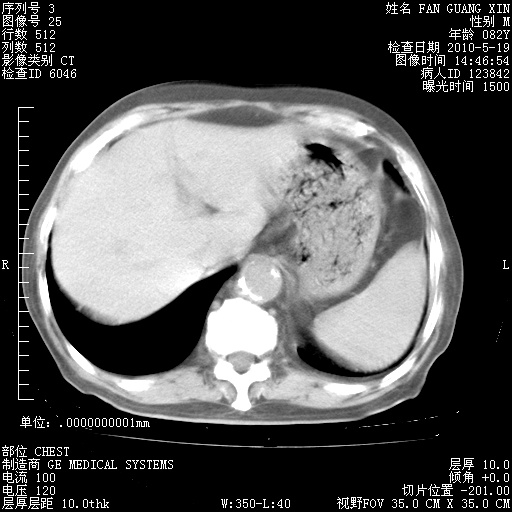

治疗3周后的肺部CT纵隔窗

再治疗10天后的肺部CT

阅读此次胸部CT,肺间质渗出性改变较入院时有吸收。目前从体温、白细胞、中性分叶明显增高,肯定存在细菌感染(发生医院感染哦,若无消化道及泌尿系统等感染的依据,肺部感染可能大)。若你院头孢哌酮舒巴坦钠耐药率较高,同意你的方案,若48小时体温仍高,可考虑使用碳青霉稀类抗菌药物,同时可予超声雾化、注意滴数时加大液体量。白蛋白33.30g/L较低哦,需加强营养等支持治疗。